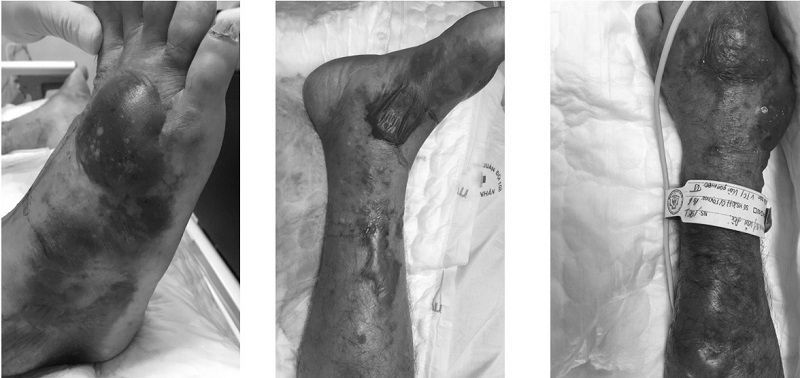

Sau vài giờ, bệnh nhân nhanh chóng rơi vào tình trạng sốc nhiễm khuẩn, suy đa phủ tạng. Ông hôn mê, suy hô hấp, suy tuần hoàn, rối loạn đông máu và chuyển hóa nặng, kèm theo tình trạng nổi ban phỏng nước, xuất huyết, hoại tử diện rộng da, cân, cơ vùng tứ chi. Bác sĩ cấy khuẩn hai mẫu máu đều dương tính với vi khuẩn Vibrio vulnificus (V. vulnificus), thường được gọi là vi khuẩn ăn thịt người.

Khi bị nhiễm trùng da và mô mềm nhanh sẽ chóng dẫn đến viêm tấy, bầm tím, phỏng nước lớn, và hoại tử cân cơ, cần phẫu thuật sớm, thậm chí cắt cụt chi.

Khi nhiễm trùng huyết thì diễn biến nhanh đến sốc nhiễm khuẩn, suy chức năng đa phủ tạng, rối loạn đông máu và rối loạn chuyển hóa nặng. Tỷ lệ tử vong rất cao. Những trường hợp qua được giai đoạn cấp tính vẫn có thể tử vong do hậu quả của suy đa tạng kéo dài.